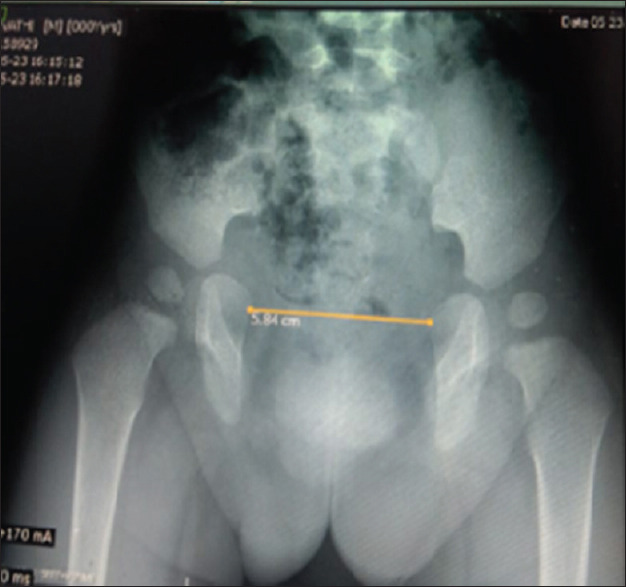

Results: The mean age of the patients in CPRE-RF was 5 months and that with only CPRE was 4.6 months. Mean pubic diastasis in Group l was 4.8± 1.07 cm and that of Group II was 4.6±1.3 cm. None of the patients in CPRE-RF had wound dehiscence or bladder prolapse while as 6 patients in CPRE alone had wound dehiscence and 1 had bladder prolapse. This difference was statistically significant. Primary bladder continence was achieved in 4 patients in CPRE-RF and 3 patients in CPRE group. Hypospadias had almost similar occurrence in the two groups. One patient in each group had bladder neck fistula.